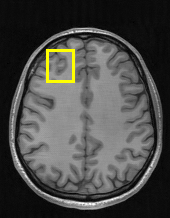

Edge preserving has always been a crucial concern in the design of reconstruction models. To improve the quality of reconstructed images and preserve image edges, some works suggested introducing edge priors in the original restoration problem to preserve image edges [4, 34]. However, they will suffer from complicated algorithm design and time-consuming training processes. Recently, some more efficient methods have been proposed to use edge maps as external guidance for image restoration. For example, Yang et al. [48] used off-the-shelf edge detectors to extract image edges from the degraded images. Fang et al. [12] predicted image edges by constructing an edge reconstruction network. Huang et al. [18] designed a novel dual discriminator GAN framework for solving fast multi-channel MRI, in which one GAN network is built for edge information enhancement. Inspired by these methods, we also consider introducing image edge prior as external guidance to MRI reconstruction since 1) image edges are prominent and distinguishable features in MRI (see Fig. 1), which can serve as a good guide to the model to recover high-frequency details; 2) the ground truth edges can be easily fetched via ordinary edge extraction operators, like Canny, Sobel, and Prewitt, which means that the edge maps can be learned in a data-driven manner. However, how to effectively utilize image edge priors to guide image reconstruction still remains a challenge. In some methods, edge information was simply concatenated with the input image and passed to the next stages. Though this is a simple way to utilize the edge priors, it may not give full play to the guiding role of the edge priors. Therefore, in this work, we want to explore a more efficient and effective mechanism to fully take advantage of image edge priors.

(a)

(b)

(c)

fastMRI is a large-scale MR dataset jointly established by Facebook AI Research and NYU Langone Health. It provides both knee and brain datasets for evaluation. In our work, we use the multi-coil knee dataset, which was acquired on three clinical 3T systems or one clinical 1.5T system using a 15-channel knee coil array. The dataset includes data from two pulse sequences, yielding coronal proton-density weighting with (PDFS) and without (PD) fat suppression. As is shown in Fig. 1, PD images usually contain more structural and prominent edge features than PDFS images, which suggests that it is more challenging to use edge guidance on PDFS datasets. Therefore, we explore the effectiveness of EAMRI on these two modalities. Following [13], for both PD and PDFS knee datasets, we separately filter out 227 volumes (8332 slices) for training and 24 volumes (1665 slices) for testing. The dataset is centrally cropped to .